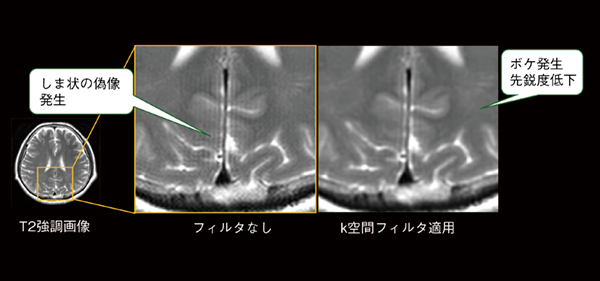

MRIの撮像原理上,データサンプリング数が少ない(マトリックスが低い)場合,大きなコントラスト差がある場所の近くにトランケーションアーチファクト(打ち切りアーチファクト)というしま状(平行な明暗線)のアーチファクトが発生します*5。その際,一般的にトランケーションフィルタというk空間フィルタを使用しますが,トランケーションアーチファクトは低減できる一方で,画像ボケが生じてしまいます(図5)。

図5 トランケーションアーチファクトの発生とk空間フィルタによる画像ボケ

有限のデータで画像再構成を行う際に生じる信号の段差が原因で発生するトランケーションアーチファクトは,平行な明暗線の偽像として現れる。この偽像を軽減するためにトランケーションフィルタというk空間フィルタを使用すると画像先鋭度が低下する。